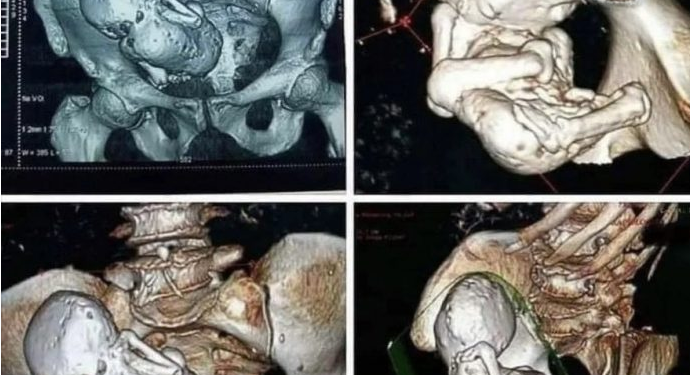

Më 25 qershor, faqja “Non Aesthetic Thing” në platformën X, me 4,8 milionë ndjekës, publikoi një imazh të një skaneri CT që tregonte një fetus të kalcifikuar, duke pretenduar se ai kishte qëndruar në trup për rreth 30 vjet. Postimi shoqërues theksonte se bëhej fjalë për një grua 73-vjeçare, tek e cila mjekët kishin zbuluar një fetus të kalcifikuar prej tre dekadash.

Raste të tilla janë jashtëzakonisht të rralla, por ofrojnë informacion të vlefshëm për komunitetin mjekësor. Në vitin 2013, ABC News raportoi për një grua 82-vjeçare nga Kolumbia, e cila kishte kërkuar ndihmë mjekësore për dhimbje në legen dhe u informua se shkaku ishte një fetus i kalcifikuar që kishte mbetur në trupin e saj për rreth 40 vjet.

Sipas Dr. Kim Garcsi nga University Hospitals Case Medical Center në Cleveland, kjo gjendje është aq e rrallë sa në literaturën mjekësore janë dokumentuar vetëm rreth 300 raste.

Lithopedioni zakonisht ndodh kur shtatzënia zhvillohet jashtë mitrës, zakonisht në bark (shtatzëni abdominale). Nëse fetusi nuk merr furnizim të mjaftueshëm me gjak dhe vdes, trupi nuk arrin ta eliminojë atë. Si mekanizëm mbrojtës, sistemi imunitar e mbështjell dhe e kalcifikon indin, në mënyrë të ngjashme me procesin që përdor për të izoluar trupa të huaj, duke parandaluar infeksionin dhe komplikacionet e tjera.